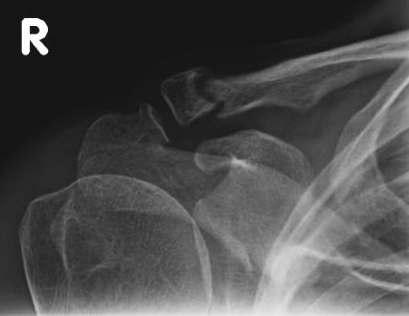

Neer Classification

Fracture lateral to the CC ligaments Non displaced

Fracture medial to the CC ligaments CCL ligaments attached to lateral fragment Medial fragment displaced superiorly |

Between conoid and trapezoid Conoid disrupted Trapezoid remains attached to the lateral fragment |

Lateral to CC ligaments Intra-articular extension Stable |

Periosteal sleeve disruption Pediatric Medial fragment displaced |

Comminuted Type II Medial fragment displaced |

Type I

Type II

Type V